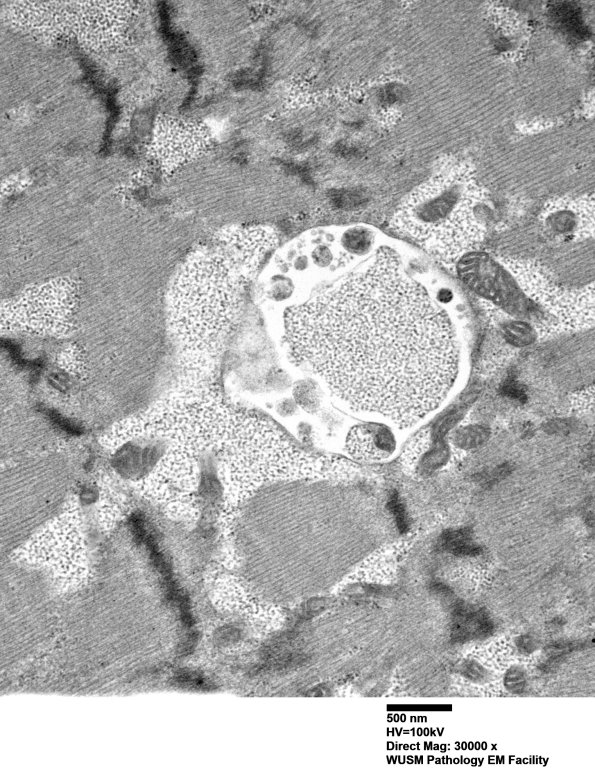

Washington University Experience | METABOLIC | Pompe Disease | 5D6 Muscle (Case 5) EM004 - Copy

In addition, a number of vacuoles containing autophagic cytosomes are accompanied by membrane bound glycogen. (electron micrographs)